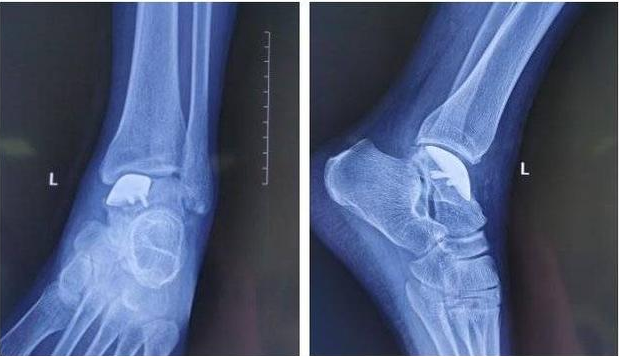

△術后X線情況